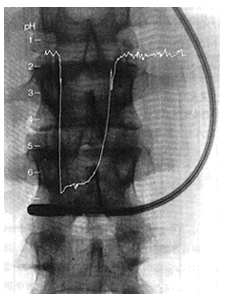

Electrodes in the Stomach

Ultrasmall compound pH electrodes can be inserted into the digestive tract to check pH of gastric juices in active status. The Living Body and pH Blood (Healthy person) 7.40 (7.36~7.44) Cerebral Fluid 7.32 Gastric Juices 1.5-8.5 Pancreatic Juices 8.6-8.8 Saliva 7.46 (7.2-7.6) Semen 7.4 (7.1-7.6) Perspiration 3.8-6.5 Urine 4.0-7.8 [Reference] Electrolyte Abnormality, Internal Medicine Mook,* No. 27 (1985),